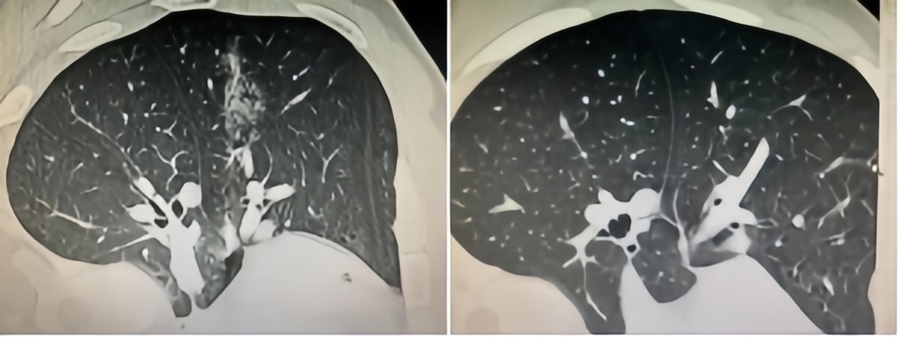

微波针是什么体检发现肺磨玻璃结节,只能随访手术二选一?“超微创”的微波消融,了解一下_https://www.jmylbn.com_新闻资讯_第3张消融术后即刻表现和消融术后6月复查

翟博表示,微波消融后是一个免疫清除和瘢痕形成的过程,个体差异较大。患者需在术后第3、9、12个月进行影像学(CT)复查评估疗效,1年后每年随访一次。年轻患者随访2年后可适当延长间隔。对于多发结节患者,随访时还需关注其他结节的变化。